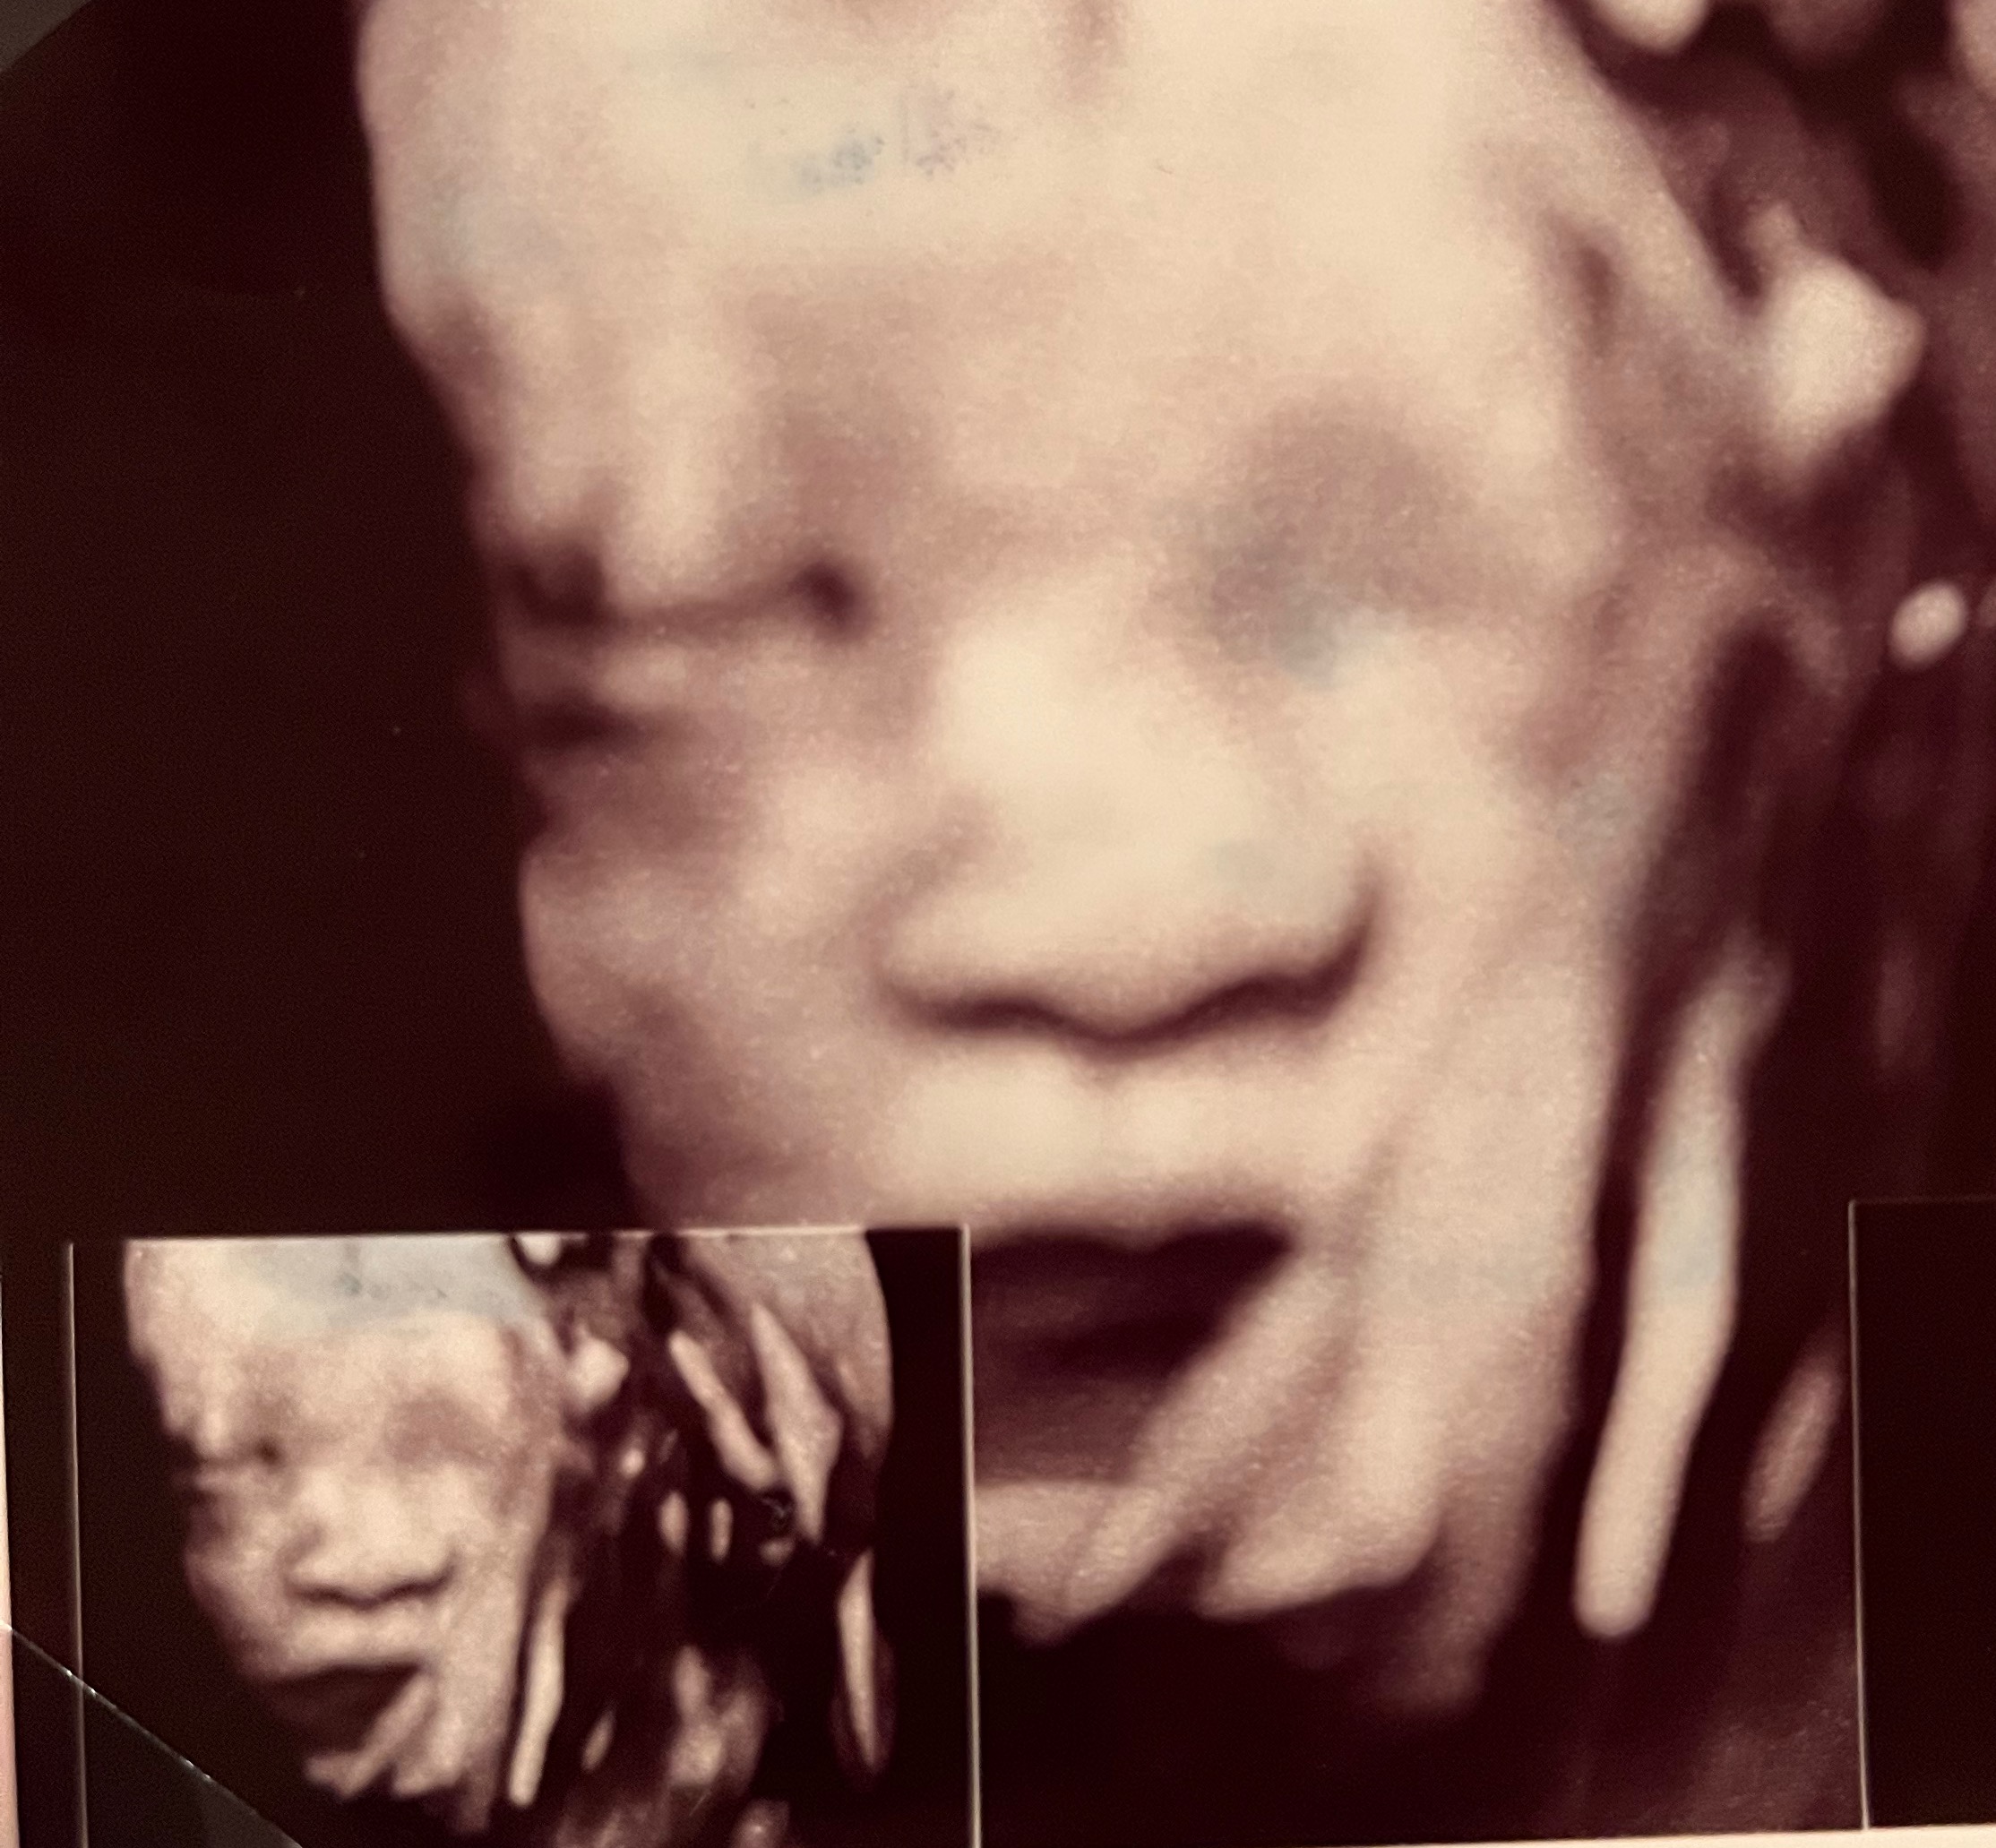

친정 엄마께도 오히려 찰흙외계인 모습이 아닌

굉장히 아가아가한 모습을 보여드릴 수 있어

좋더라구요! ㅎㅎ 엄마는 저 가졌을땐 이런게

없었다며 엄청 신기해하시고 신나하셨어요!

아! 원장님께서 검사결과 면담해주실때

제일 먼저 하신말씀이 정면으로 보면 코가

낮아보여서 엄마들이 많이 실망하는데,

이 사진으로 보면 원래 다 그렇다,

양수에 불어있어서 그렇기도 하고 정면샷은

더욱 더 그렇기도 하니까 미리 실망안해도 된다

하시더라구요! 실제로 옆모습나온 사진은

코가 있습니다 있어!! ㅎㅎㅎ